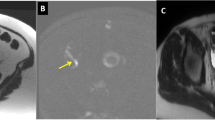

T1-W VIBE imaging in a 7-year-old boy with embryonal rhabdomyosarcoma who had routine surveillance imaging. This study was performed without sedation but with the assistance of a child life specialist. a Axial Cartesian T1 VIBE with fat suppression image obtained with a 20-s breath-hold shows artifact from breathing at the interfaces of the solid organs, particularly the liver. b Axial non-Cartesian Star-VIBE with fat suppression image obtained during free-breathing as a continuous acquisition over 2 min. In contrast to (a), the Star-VIBE is motion robust, with clean margins at the edges of the liver, spleen, pancreas and kidneys. c, d Post-contrast coronal T1-W VIBE (c) and Star-VIBE (d) side-by-side show the superior resolution and clarity of the structures with Star-VIBE. VIBE volume-interpolated breath-hold examination

Diffusion-weighted imaging in a 14-year-old boy with intermittent severe abdominal pain, lower abdominal pain on exam, and concern for constipation. The boy was referred for MR enterography. a Unexpectedly, diffusion-weighted imaging demonstrates hyperintense signal of the appendix. b Corresponding apparent diffusion coefficient map shows corresponding low signal, compatible with restricted diffusion in this case of acute appendicitis